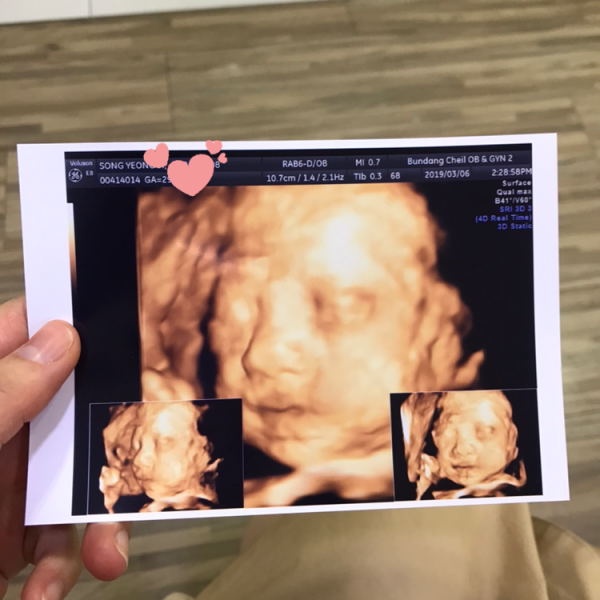

2019-04-29안녕하세요. 이현준님, 먼저 아내를 생각하는 마음이 가득 담겨진 편지라 더욱 더 따뜻함이 전해지는 것 같습니다. 더불어 예쁜 사진들과 이은성 과장님을 비롯한 많은 직원분들 한 분 한 분을 잊지 않고, 이렇게 정성스럽게 써주신 편지에 본원의 모든 직원들이 놀람과 감동을 크게 느켰습니다. 본원의 모든 선생님들이 친절한 것 같다는 말씀도 정말 감사드립니다.^^예쁘게 완성한 펠트만큼와 초음파 사진 속 현준님의 아이도 너무 사랑스럽고, 예쁩니다. 바쁘신 와중에 감사의 편지를 남겨주셔서 감사합니다. 전해주신 감사의 편지에 보답할 수 있도록 더욱 친절하고, 높은 의료 서비스로 발전하는 분당제일여성병원이 되겠습니다.